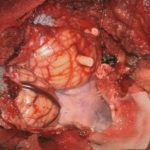

711

'25年12月

60代

良性頭蓋咽頭腫

頭蓋内腫瘍摘出術